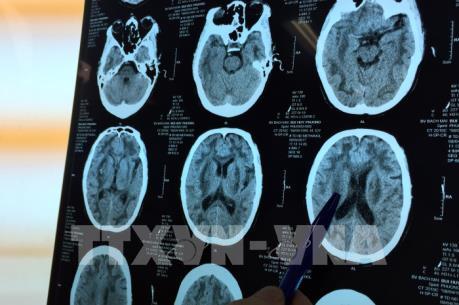

Uống rượu có chừng mực cũng gây hại tới não bộ

Không phải chỉ nghiện rượu mới là có hại cho thần kinh mà ngay cả việc uống rượu ở mức độ "vừa phải" cũng có thể gây ra những tổn hại nhất định cho não bộ và sức khỏe thần kinh.